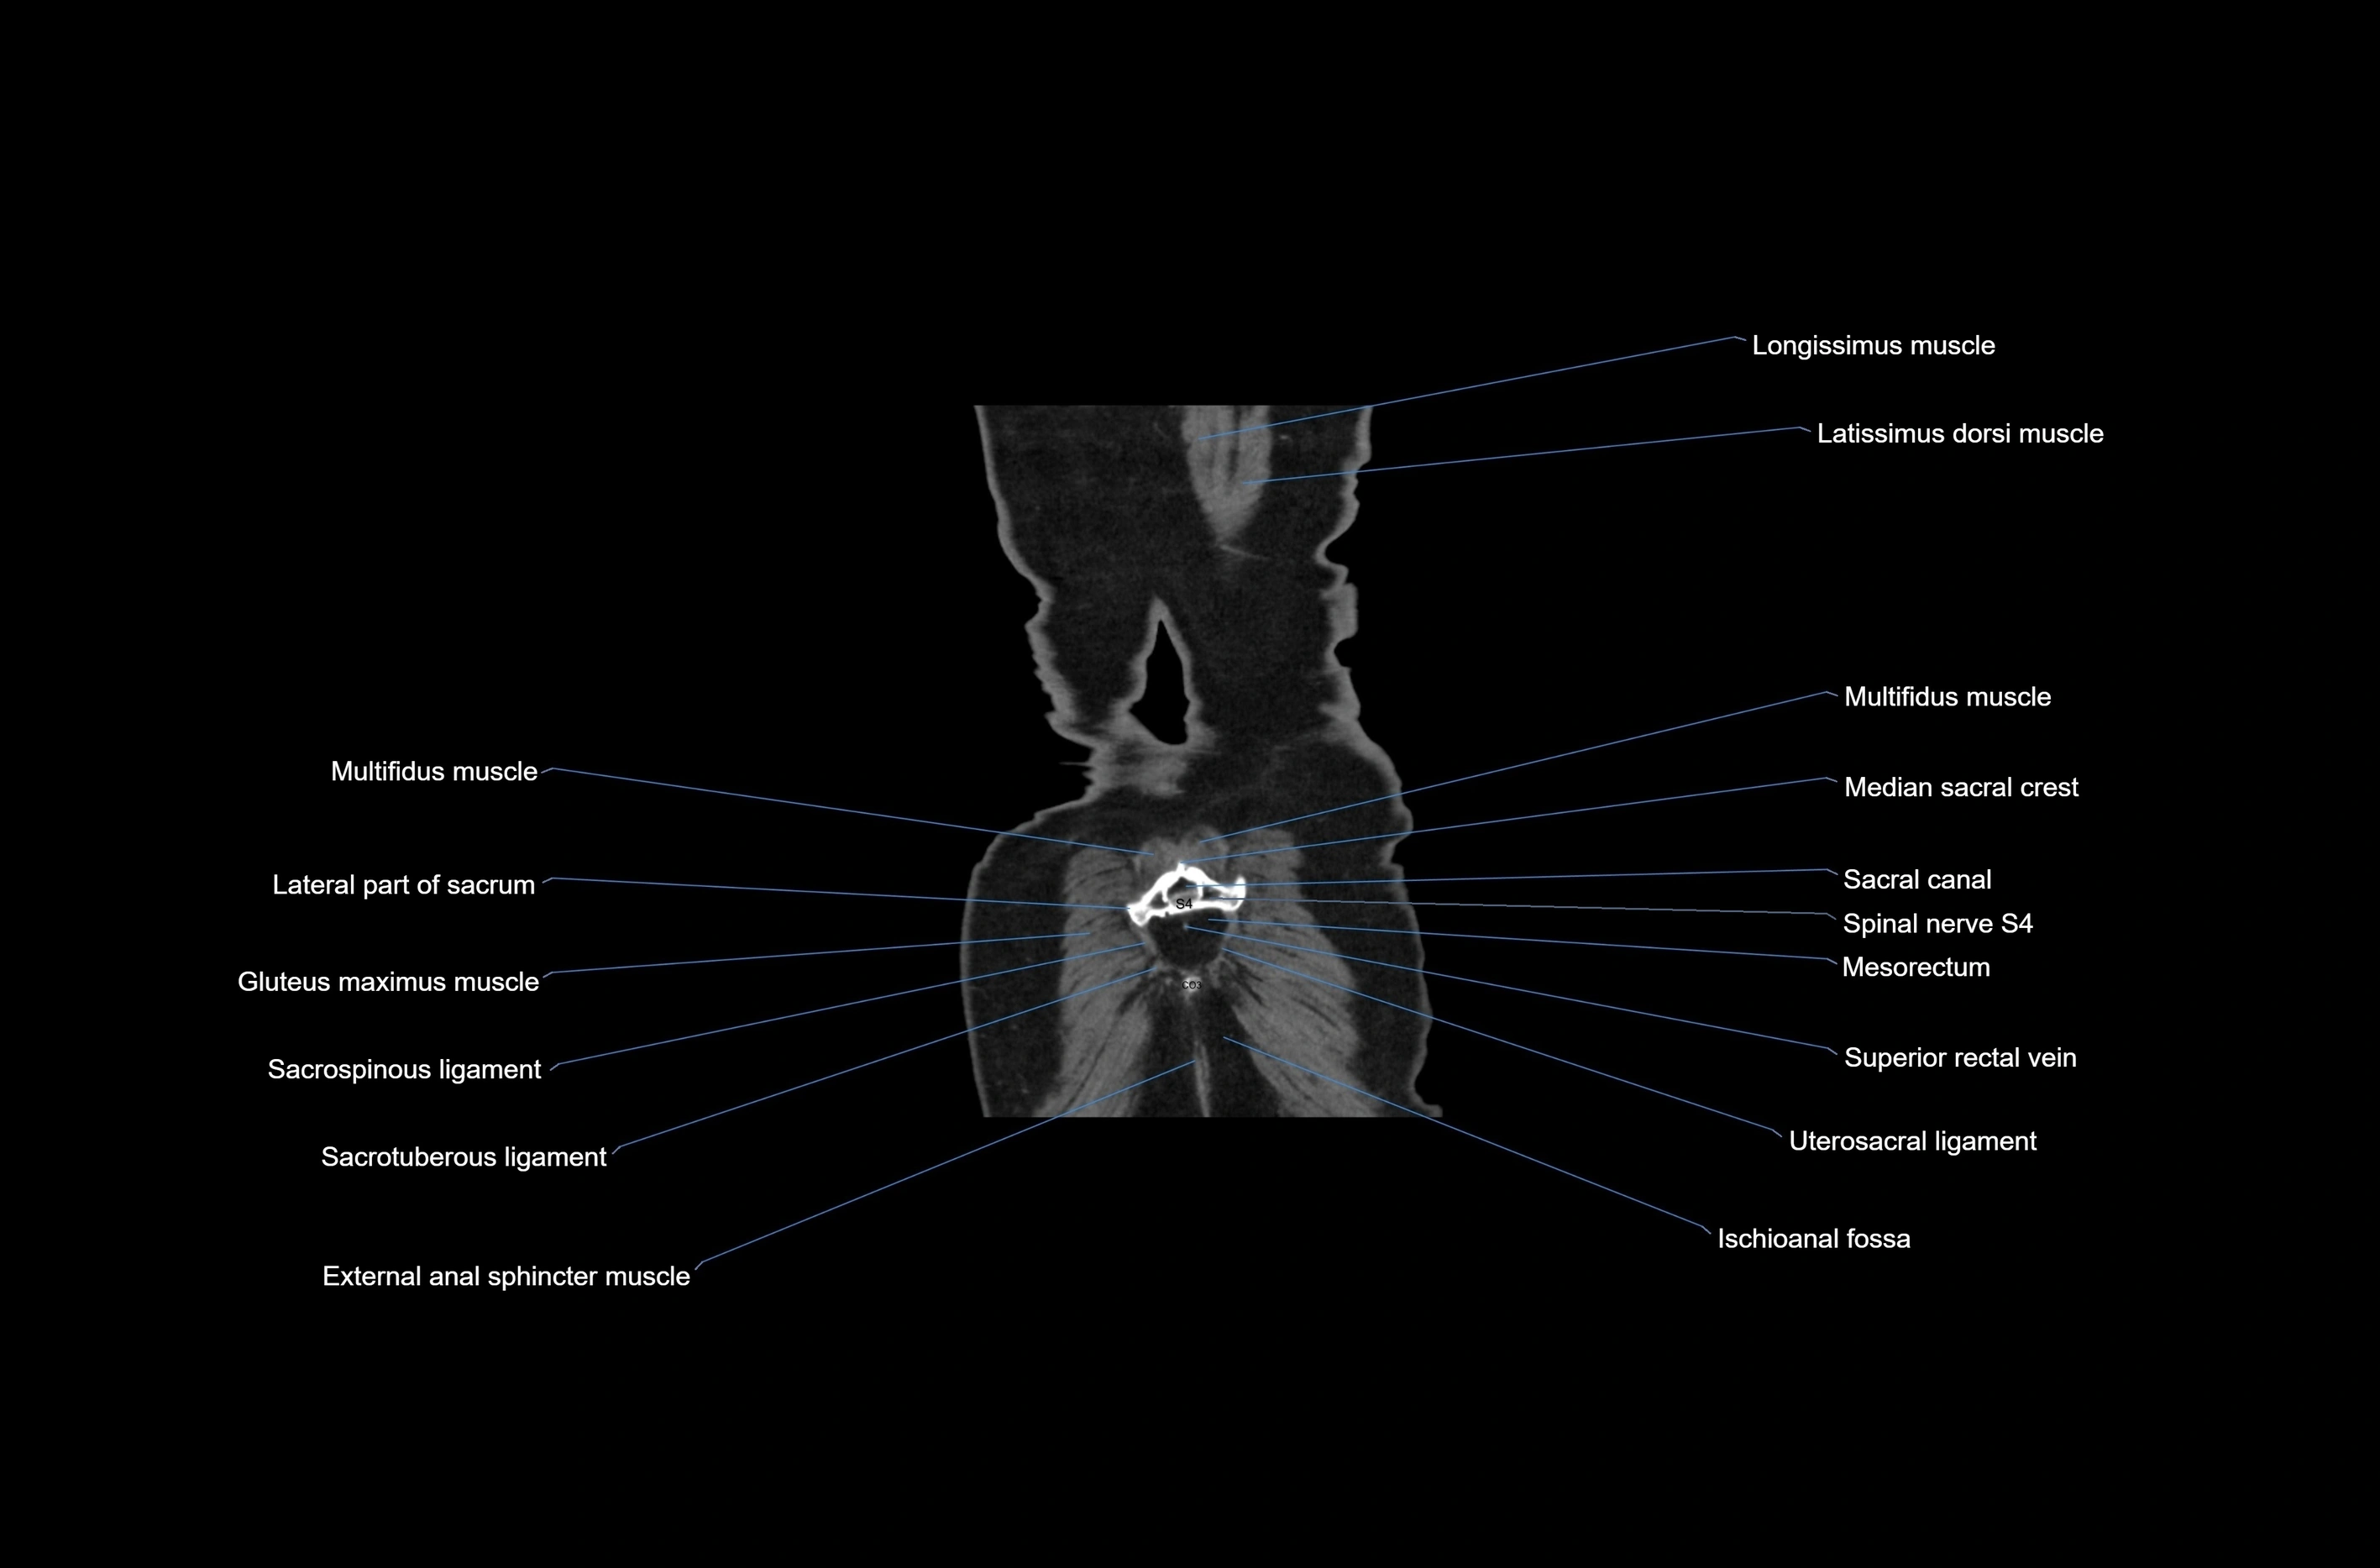

- Lateral part of sacrum

- Latissimus dorsi muscle

- Median sacral crest

- Sacral canal

- Sacrospinous ligament

- Sacrotuberous ligament

- Spinal nerve S4

- Ischioanal fossa

- Gluteus maximus muscle

- Mesorectum

- Superior rectal vein

- Uterosacral ligament